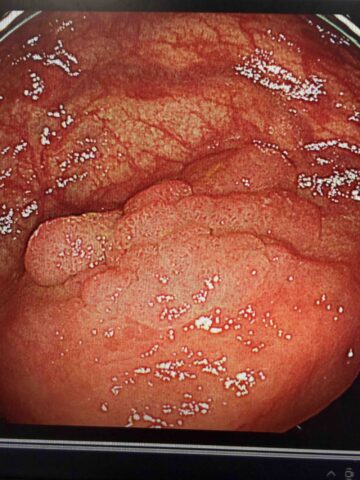

大腸ポリープを早めに取ると、がん予防の効果がこんなに違う!

近年、日本では大腸がんが男女あわせて最も多いがんのひとつになっています。がんによる死亡数の部位別順位では男性では2位 (1位は肺がん)、女性では1位です。その多くが、「ポリープ」から始まることをご存じでしょうか。ポリープって何?大腸の内側(...